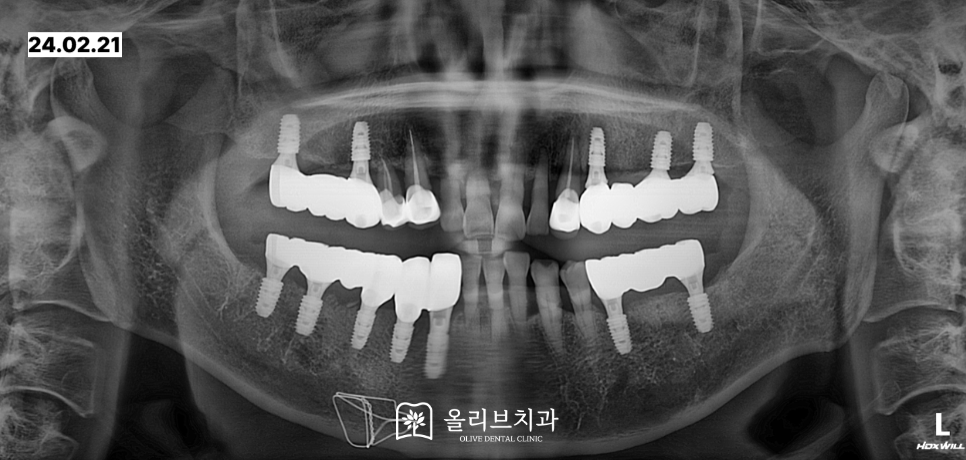

보철치료 단계에서는 임시치아를 통해 교합을 점검하고 적응할 수 있도록 시간을 두었고, 최종적으로는 심미성과 강도가 우수한 지르코니아 보철물로 완성하여 오랫동안 사용할 수 있도록 했습니다.

비산동치과 임플란트 식립 이후 약 3개월이 지나서 아래의 최종보철을 완성하였습니다.

상악은 한 달정도의 시간을 더 기다린 뒤 최종보철을 완료하였습니다.